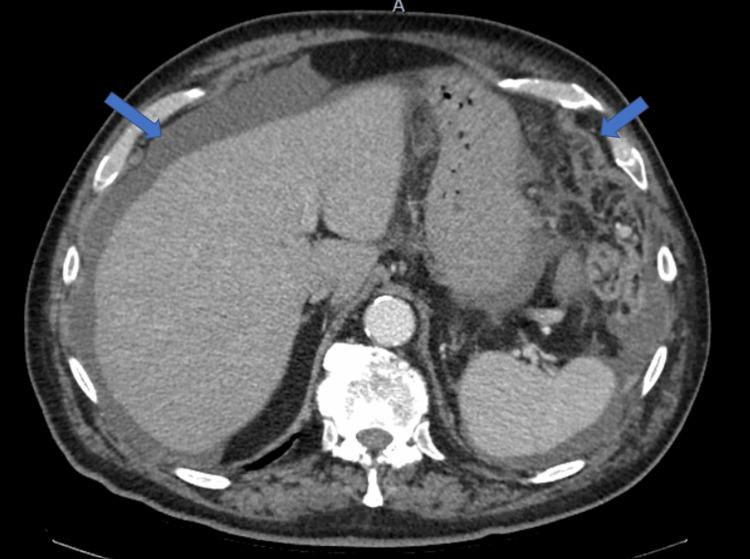

Cutaneous melanoma is an aggressive skin cancer with a high propensity for distant metastasis. Peritoneal metastasis from cutaneous malignant melanoma is extremely rare and associated with a low five-year overall survival rate. This report reviews a case of a 78-year-old man with peritoneal carcinomatosis after a wide local excision of a T1a invasive malignant melanoma of the scalp 10 months prior. Although rare, patients with a recent history of melanoma who present with obscure or odd symptoms should be worked up for metastatic disease by their surgeon or medical oncologist. Carcinomatosis can develop, and early treatment with immunotherapy has been shown to improve five-year overall survival and progression-free survival in patients with advanced melanoma.

皮肤黑色素瘤是一种侵袭性皮肤癌,极易发生远处转移。皮肤恶性黑色素瘤的腹膜转移极为罕见,且五年总生存率较低。本报告回顾了一例78岁男性病例,该患者在10个月前对头皮T1a期侵袭性恶性黑色素瘤进行广泛局部切除后发生了腹膜癌转移。尽管罕见,但有黑色素瘤近期病史且出现不明或异常症状的患者,外科医生或医学肿瘤学家应排查其是否患有转移性疾病。腹膜癌转移可能会发生,免疫疗法早期治疗已被证明可提高晚期黑色素瘤患者的五年总生存率和无进展生存率。